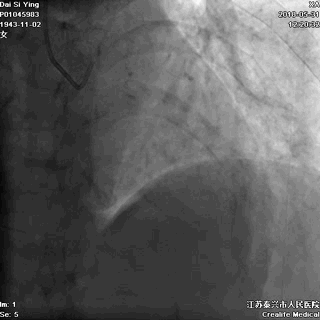

我们曾接诊过一个姓戴的老奶奶,79岁,她出现胸痛后,先是自己在家观察和处理,过了9小时还没缓解,才赶往医院。我们马上进行了急诊手术,很成功,命是保住了,但因为太迟来就诊,心脏功能已经严重受损。

术后,她反复出现心衰,生活质量明显下降。  血管闭塞

血管开通

记住:时间就是心肌,时间就是生命。每耽误一分钟,就意味着更多心肌细胞坏死。